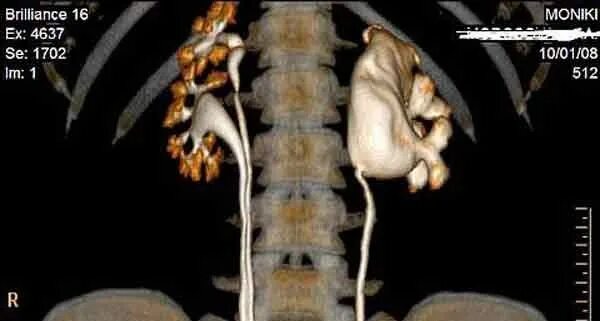

Гидронефроз почки после операции